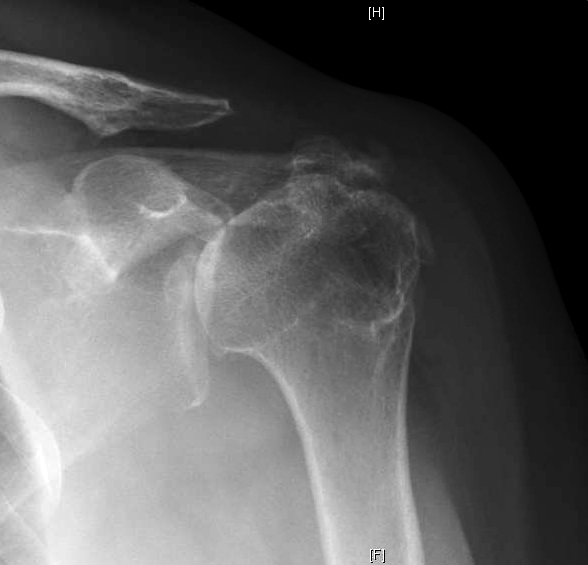

Here's the example of a lady in her mid sixties with a failed cuff repair. Two years after that surgery she presented to us with a weak and painful shoulder. She was taking prednisone, methotrexate and Humira for her rheumatoid arthritis. She had active elevation to 110 and passive elevation to 160 degrees. Her x-rays at this time are shown below.

Before his left shoulder surgery his films were as shown below and he reported the ability to perform only 5 of the 12 Simple Shoulder Test functions. He was able to elevate his arm to over 90 degrees and had no anterosuperior instability.

Two years ago he presented with a similar situation in his right shoulder. His SST score was 3/12. He had active elevation of 100 degrees without anterosuperior escape. His preoperative x-rays shown below.